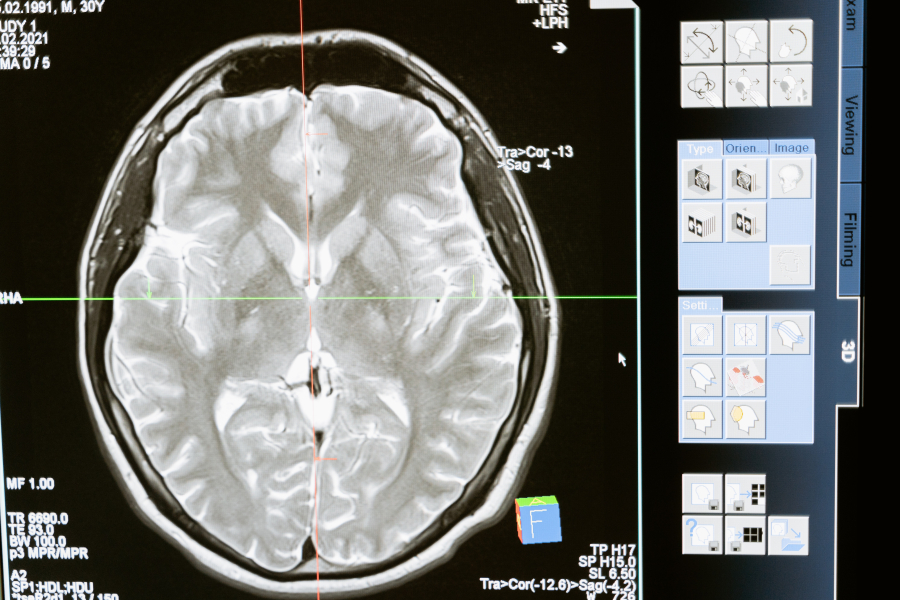

Διαφέρει από το εγκεφαλικό εμφύτευμα που δημιούργησε η εταιρεία του Elon Musk επειδή η διαδικασία είναι λιγότερο επεμβατική και το τσιπ βρίσκεται στην επιφάνεια του εγκεφάλου και όχι στον ιστό.

Το εμφύτευμα, που ονομάζεται Layer 7 Cortical Interface, είναι μια λωρίδα από εύκαμπτο, λεπτό υλικό φιλμ, σαν ένα κομμάτι ταινίας Scotch.

Η λωρίδα φέρει ηλεκτρόδια και έχει πάχος που είναι το ένα πέμπτο μιας ανθρώπινης τρίχας, γεγονός που τη βοηθά να προσαρμόζεται στην επιφάνεια του εγκεφάλου χωρίς να καταστρέφει κανένα ιστό.

Για την εμφύτευση της συσκευής, οι χειρουργοί κάνουν μια πολύ λεπτή σχισμή στο κρανίο και την εισάγουν σαν να βάζουν ένα γράμμα σε ένα κουτί.

Η συσκευή λειτουργεί με τη συλλογή εγκεφαλικών σημάτων, την ερμηνεία τους και την έκδοση εντολών σε ένα συνδεδεμένο μηχάνημα ανάλογα με το εγκεφαλικό σήμα που λαμβάνεται.